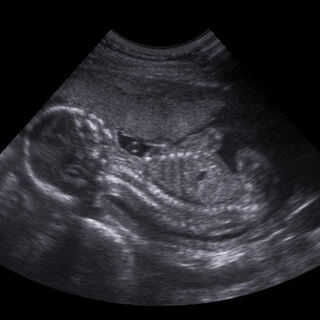

بعد انغراس البويضة يكون الطفل في هذه المرحلة صغيرًا جدًّا، ولكنه ينمو بشكل سريع جدًا، وسرعان ما يصبح بحجم حبة الفاصولياء ويتحرك باستمرار، كما أن نبض القلب يكون سريعًا وتتكون أمعاؤه ووجه، لكن كيف يبدو البطن في هذه المرحلة أي الأشهر الثلاثة الأولى من الحمل، إليك التفاصيل:

مراحل كبر بطن الحامل من (الشهر الأول - الشهر الثالث)

يختلف حجم وشكل البطن من شهر لآخر، إليك مراحل كبر بطن الحامل في الأشهر الثلاثة الأولى من الحمل:

1. الشهر الأول (الأسبوع 1 - 4): لا يتغير في هذه المرحلة حجم البطن، حيث لا يتعدى حجم الجنين 2 سنتيمتر.

2. الشهر الثاني (الأسبوع 5 - 8): يبقى البطن ثابتًا، ولا يوجد فرق في حجم وشكل البطن، لأن حجم الجنين يصبح حوالي 2 - 2.5 سنتيمتر.

3. الشهر الثالث (الأسبوع 9 - 13): تظهر في هذا الشهر نتوءات صغيرة أسفل البطن، حيث يبلغ طول الجنين حوالي 10 سنتيمتر.